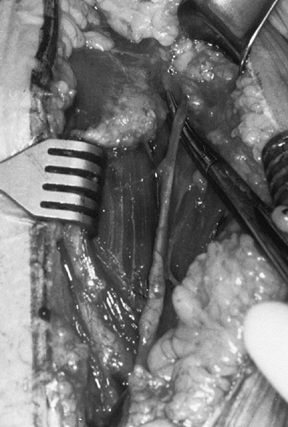

division (Fig. 101.22, Fig. 101.23).

lengthening, as discussed previously.

Figure 101.22. Divide the subscapularis from superior to inferior in its entirety.

Figure 101.23.

Division of the subscapularis and capsule provides access to the joint.

Avoid the biceps tendon at the superior margin. Cauterize the anterior

humeral circumflex vessels at the inferior margin. -

Place several nonabsorbable sutures in the proximal subscapularis tendon for identification, retraction, and reattachment (Fig. 101.24).